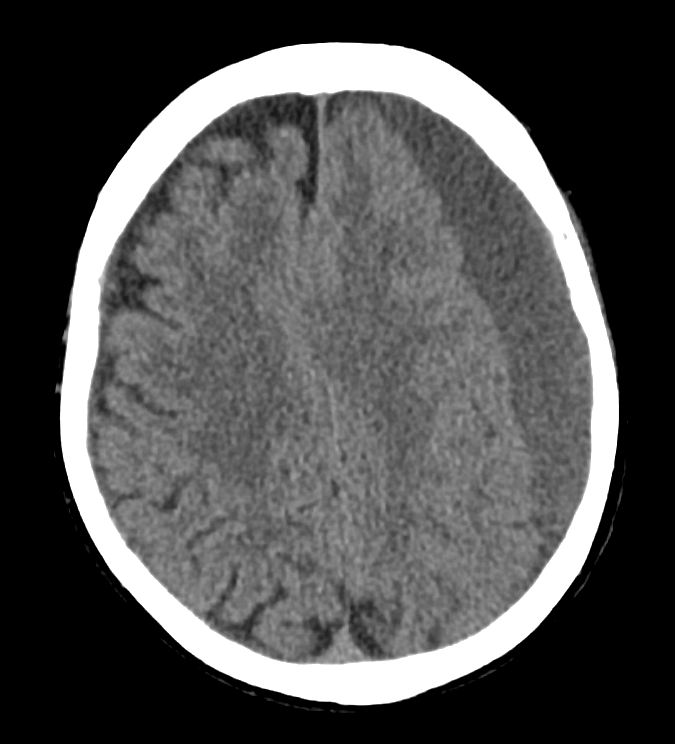

Subdural hematomas are collections of blood between the brain’s tough dural covering and thin arachnoid covering. The most common cause is tearing of venous structures, and it can be caused by minor trauma. Patient’s on anticoagulants, thrombocytopenia or significant cerebral atrophy are at higher risk.

Clues to the presence of subdural hemmorhages include:

- No extension into the sulci (as would be seen in subarachnoid bleeding)

- Concave shape, like a crescent

- Not typically associated with skull fractures, unlike epidural hematomas

- Typically slowly expanding